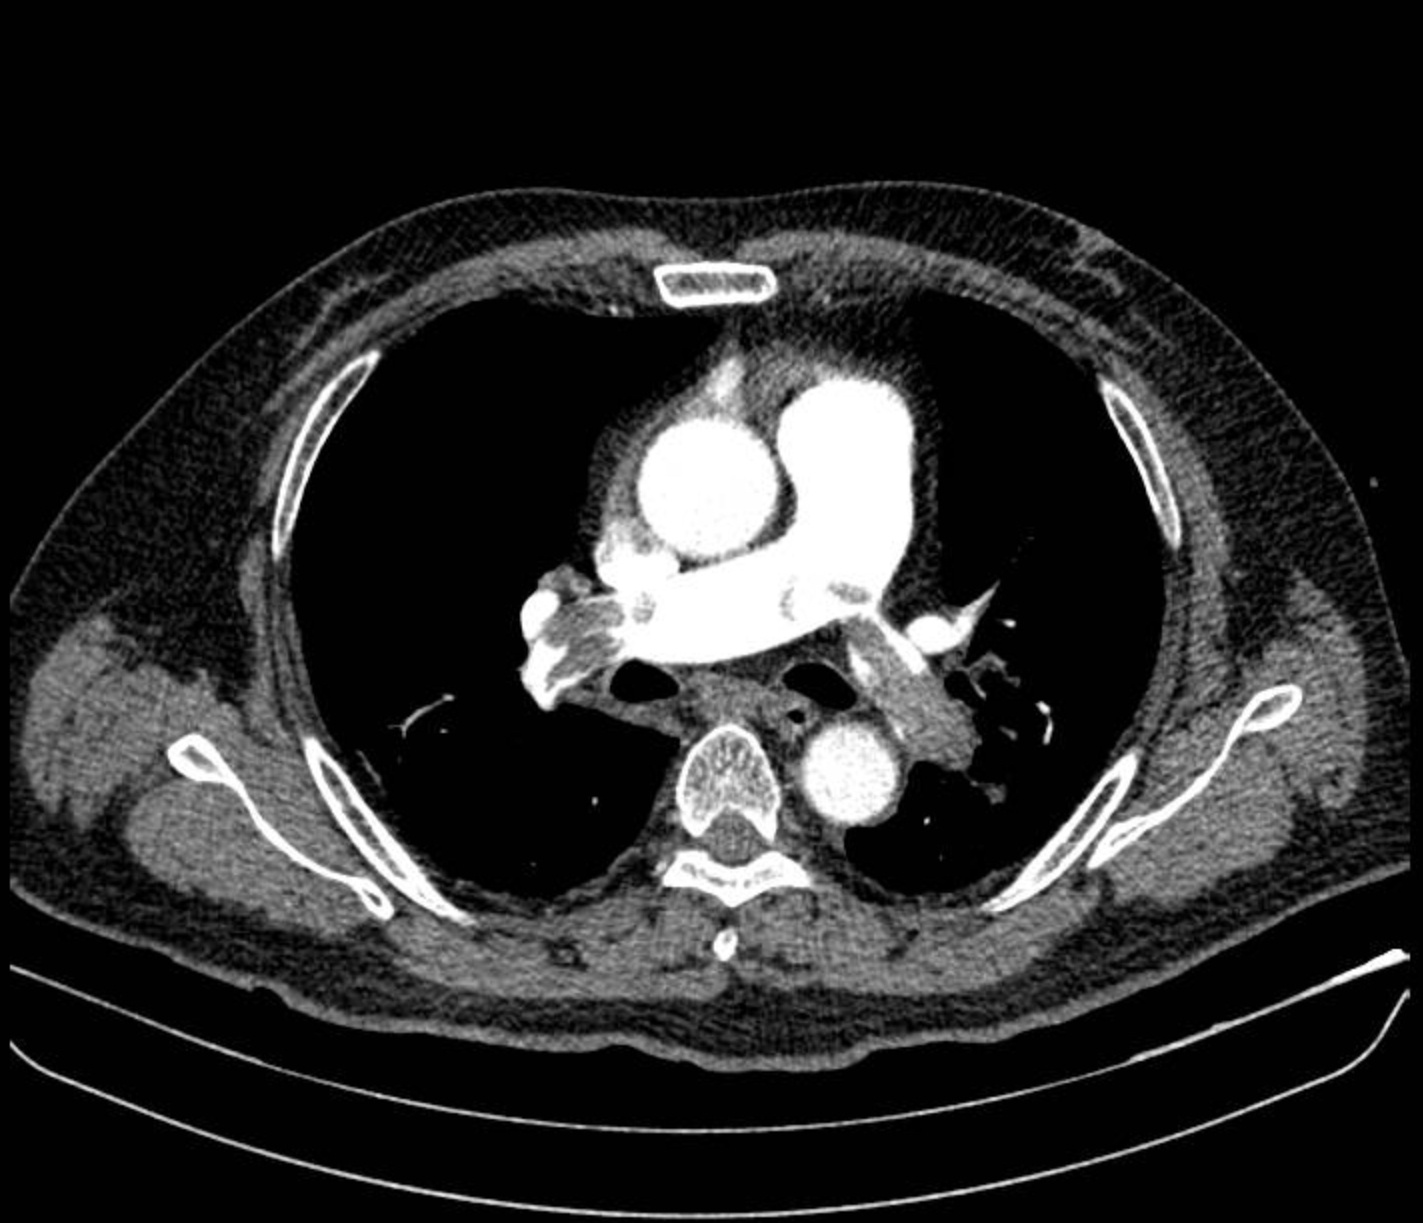

Bệnh nhân nhanh chóng được dùng thuốc vận mạch để ổn định huyết áp, chụp CT mạch máu phổi. Kết quả cho thấy huyết khối lớn bít tắc hai nhánh động mạch phổi. Các bác sĩ khoa Cấp cứu phối hợp Khoa Hồi sức tích cực xác định đây là trường hợp sốc tắc nghẽn do thuyên tắc phổi nguy cơ cao.

Hình ảnh chụp CT mạch máu phổi cho thấy huyết khối lớn bít tắc động mạch phổi hai bên. Ảnh: BVCC.